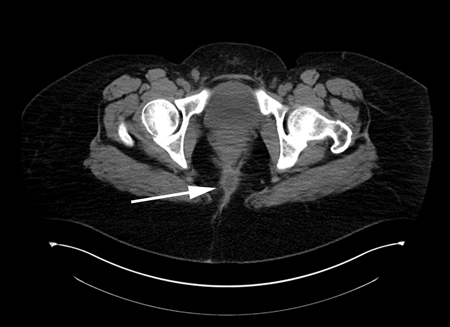

Abscesso anorretal

Tomografia computadorizada (TC) demonstrando um abscesso perirretal

Do acervo do Dr. C. Neal Ellis; usado com permissão